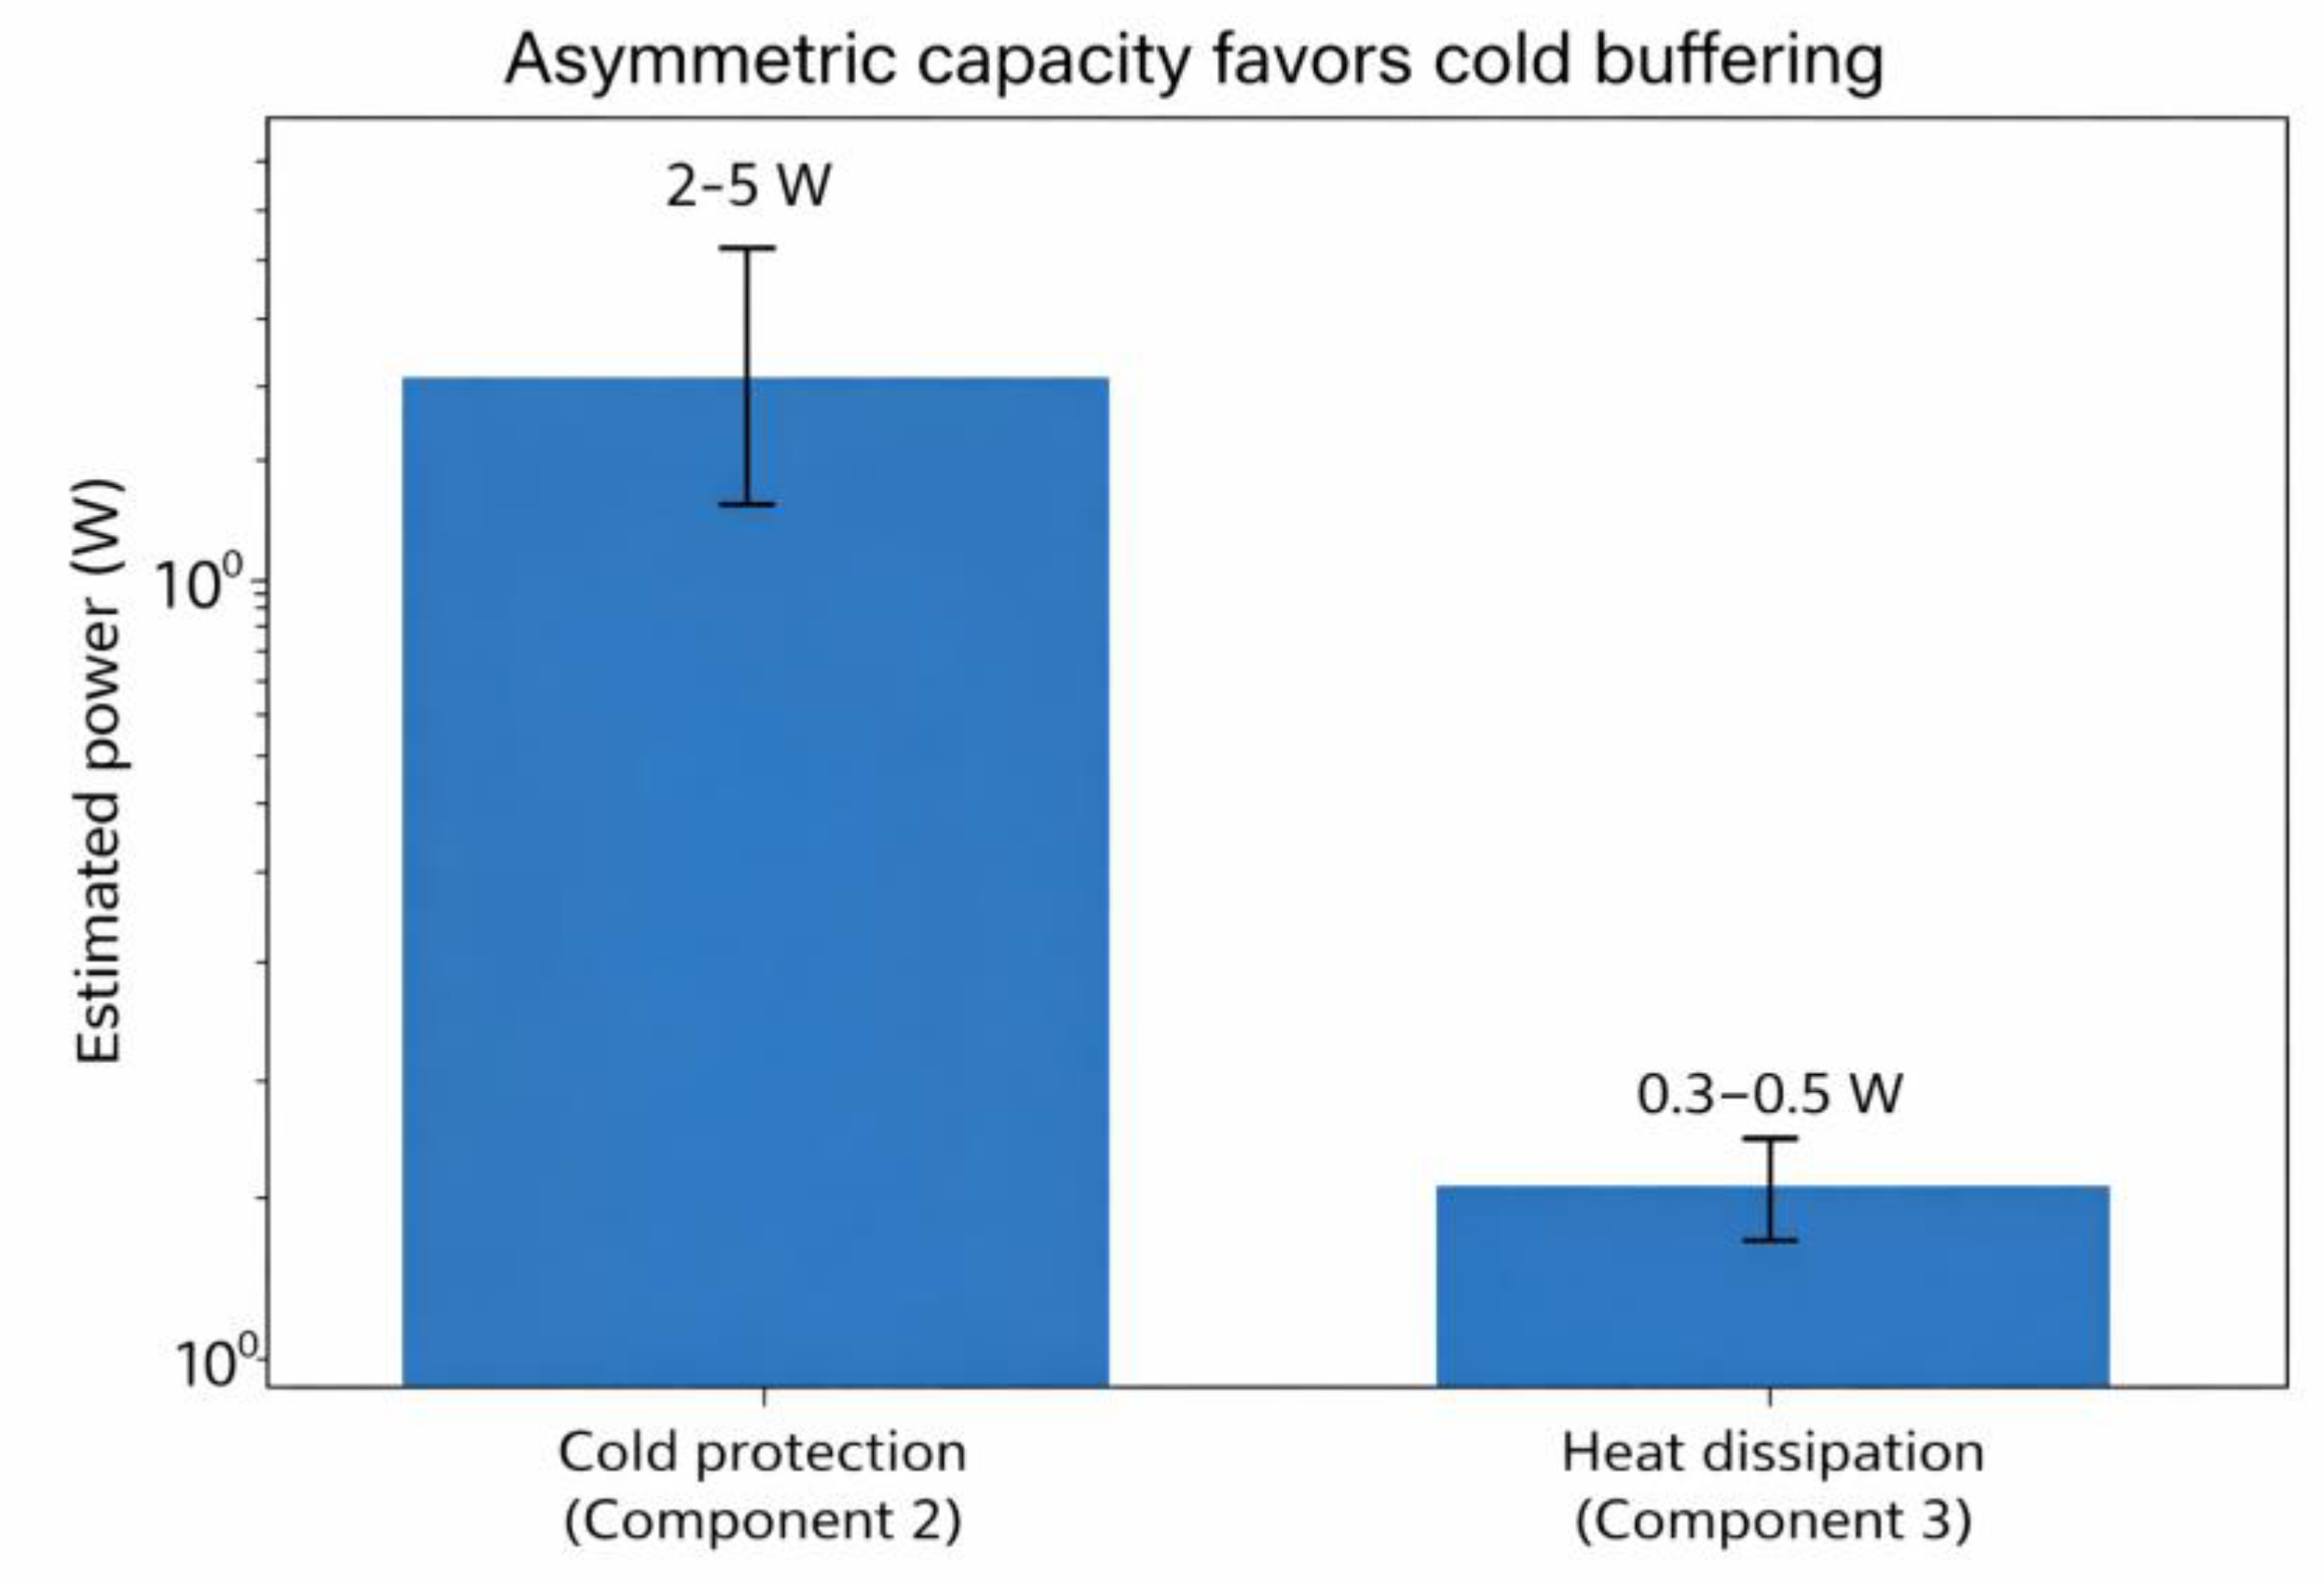

Asymmetric Architecture: Thermodynamic Rationale